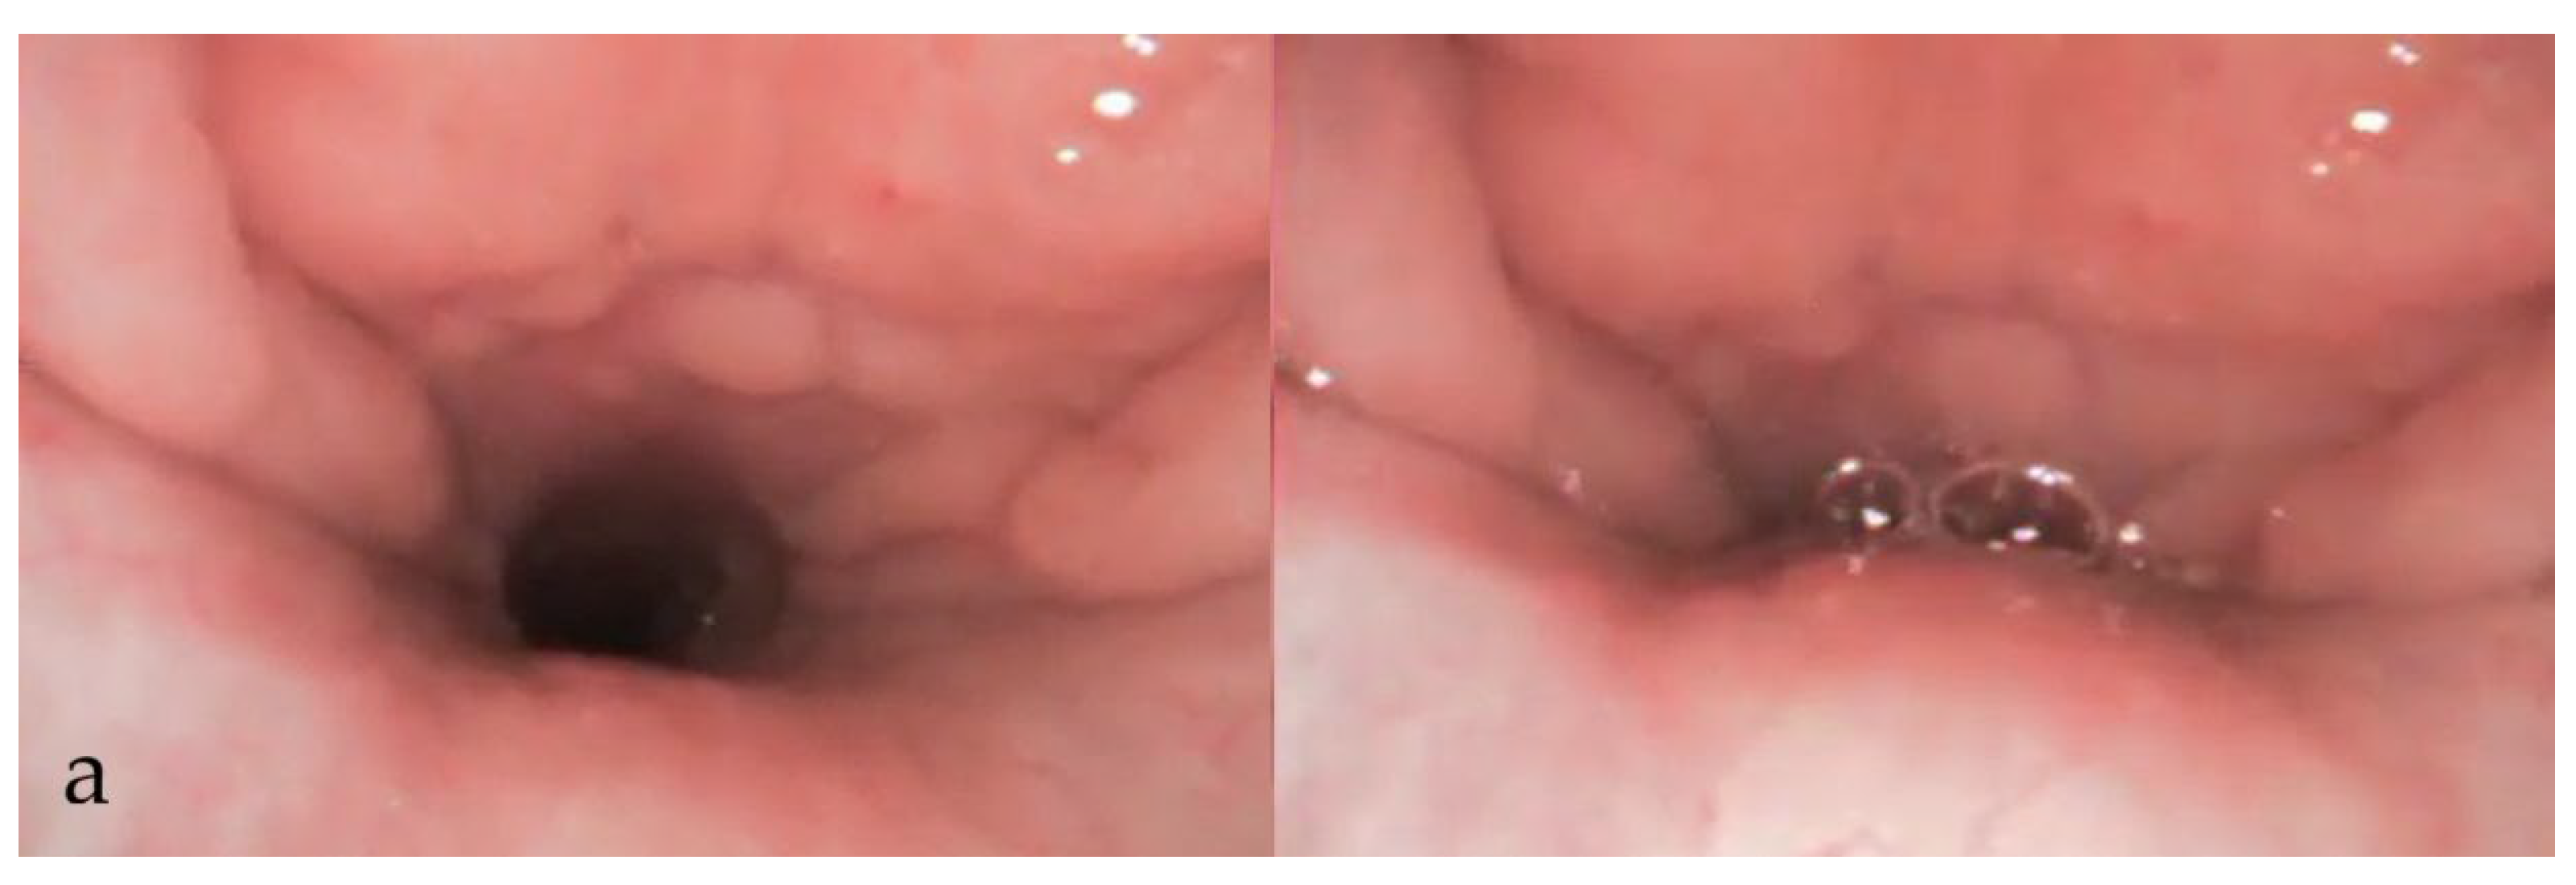

3.3. During DISE (Figure 1)

3.3.8. Documentation